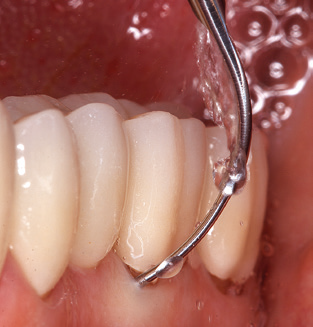

The current working concept for SPT

Updating the patient’s medical history is an important aspect of SPT and should occur at least once per year. It helps the dental team to identify and document any new risk factors. Especially when a patient is treated over many years, it is important to establish whether patient-specific and general health risk factors have changed. This primarily concerns a heightened risk as a result of diabetes, but other general conditions (cardiovascular disease and neoplasia) can also produce a modified risk profile as a result of the treatment performed and medication administered. Accordingly, updating the medical history as part of SPT is very important, as a modified risk profile may trigger the need to adapt the treatment interval. In the next step, it is important to afford the diagnostics due attention. Whilst instruments are a central aspect of SPT, findings and their documentation must never be neglected. The periodontological findings are essential for a good diagnosis; increases in the pocket depths and the BOP index are clear indicators of advancing periodontal and peri-implant disease. As such, the team should not shy away from probing implants too, with the aim of gathering the requisite data. At the same time, it is important to use periodontal probes with millimetre markings. Metallic probes have already been used for determining pocket depths around natural teeth for decades. In the case of implants, the challenge of recording correct and reproducible pockets depths is even greater. As the discrepancy between the implant diameter and the contour of the superstructure regularly results in overcontouring of the superstructure, flexible probes which still feature millimetre markings are a sensible solution for measuring pocket depths around implants (e.g., Colorvue Kit PCV11KIT6, Hu­Friedy; Fig. 4).

Fig. 4: Flexible probes with millimetre markings are recommended for the probing of dental implants (e.g. Colorvue Kit PCV11KIT6, Hu­Friedy). – Fig. 5a and b: A straight working tip (1P, W&H Dentalwerk Bürmoos GmbH) is a suitable instrument for use on all natural teeth. – Fig. 6: Curved working tips (3Pr/3Pl, W&H Dentalwerk Bürmoos GmbH) lend themselves to the processing of difficult-to-reach areas of the tooth and root surfaces (e.g. furcations). – Fig. 7: The tapered, hexagonal implant cleaning tip (1I, W&H Dentalwerk Bürmoos GmbH) permits atraumatic and efficient cleaning of the crown and abutment surfaces. – Fig. 8: Titanium and carbon curettes are suitable instruments for the manual cleaning of the implant surfaces.

Good illumination of the working field facilitates the process considerably. The system used by the authors achieves this thanks to a 5x LED ring integrated in the handpiece. Naturally, a range of working tips for different indications is also offered. A straight, universally employable tip is the basic instrument required for machine cleaning of natural teeth (Fig. 5a and b). Curved tips, which allow access to exposed furcations, are also available for hard-to-reach areas in the posterior region (Fig. 6).